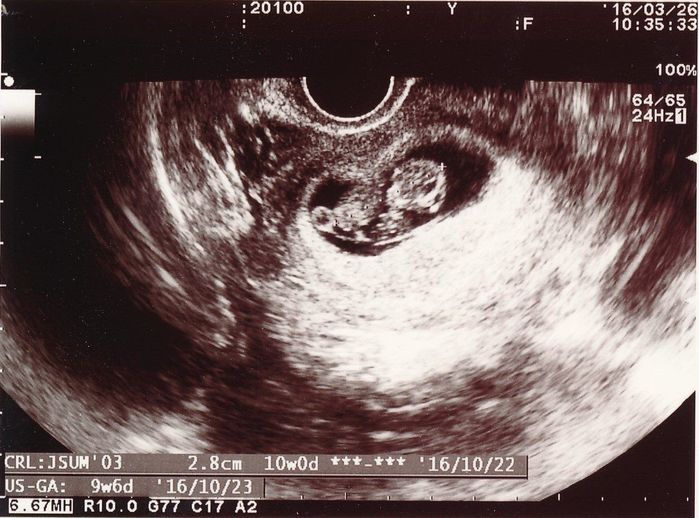

妊娠9週目のエコー写真

赤ちゃんは2.8cmになりました。ハート型のように写っている胎嚢の右側にあるのが頭で左側が体です。人間らしくなってきたのが嬉しかったのを覚えています。マクロビオティックの先生からいただいたアドバイスを元に、食事内容や体を冷やさないことなどに注意をしながら慎重に毎日を過ごしていました。